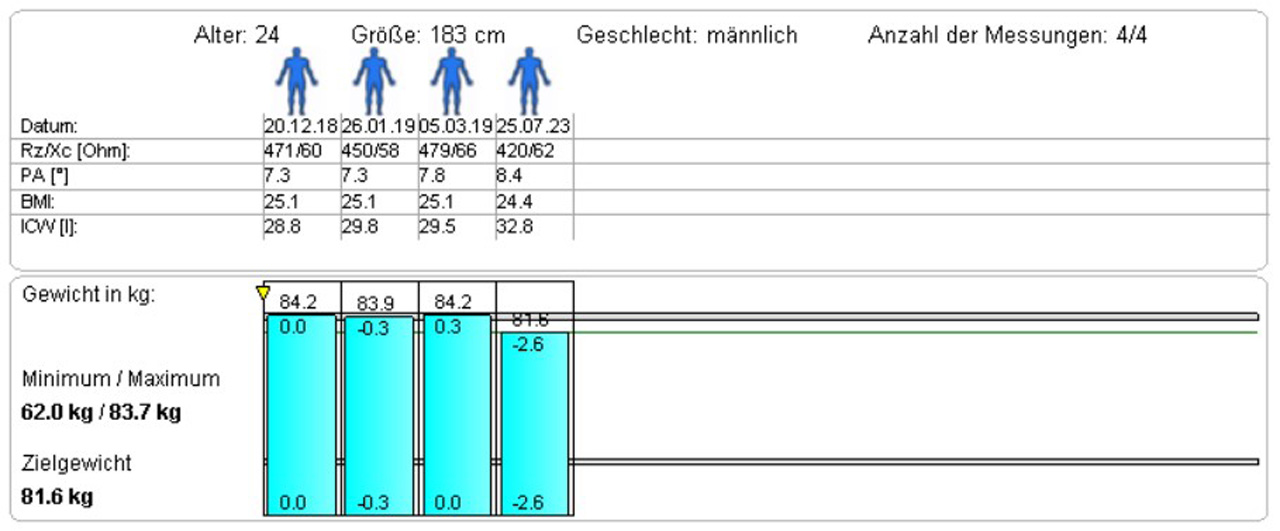

Darstellung der Auswertungs-Ergebnisse

Die Entwicklung und die Wirkungen der Trainingsmassnahmen und begleitender Ernährungsumstellungen können mittels Balkendiagramm dargestellt werden.

Dieser junge Patient macht seit Jahren Krafttraining. Man kann sehen, dass sich der Fettgehalt massiv reduziert hat, die BCM deutlich zugenommen hat und das ECW abgenommen hat.